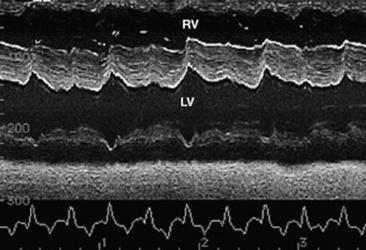

Echocardiographic examination is performed in a systematic way, using standardized images to obtain information about chamber size, wall thickness, myocardial function, valve appearance, valve function, great vessels, blood flow, and presence of abnormal structures or echodensities. The standard equine or bovine echocardiogram is performed from the right parasternal window (the right fourth intercostal space in horses and third intercostal space in ruminants) with a 2.5-MHz transducer. Higher-frequency transducers should be used to examine younger animals, South American camelids, and small ruminants. Both long- and short-axis views of all cardiac structures should be evaluated. The cardiac valves should be carefully examined for any abnormalities of structure or function (thickening, prolapse, ruptured chordae tendineae, fenestrations, flail valve leaflet, vegetative lesion, or high-frequency vibrations). The relative size, shape, and relationship of the cardiac chambers and great vessels should be assessed, and an evaluation of myocardial function and blood flow performed. Standard measurements of left ventricular internal diameter, left ventricular free wall thickness, interventricular septal thickness, and right ventricular internal diameter should all be obtained at end diastole and peak systole from the M-mode echocardiogram. The diameter of the aortic root and left atrial appendage, the distance between the interventricular septum and the peak opening of the septal leaflet of the mitral valve (septal to E point separation), and the left ventricular ejection time (ET) should also be determined. End-diastolic measurements are obtained at the Q wave of the ECG, whereas peak systolic measurements are made from the peak downward deflection of the interventricular septum. Calculations of fractional shortening (FS) and ejection fraction (EF) can then be performed to assess left ventricular function using the following formulas:

image

in which LVIDd is the left ventricular internal diameter at end diastole (cm), LVIDs is the left ventricular internal diameter in systole (cm), and ET is the left ventricular ejection time (sec).